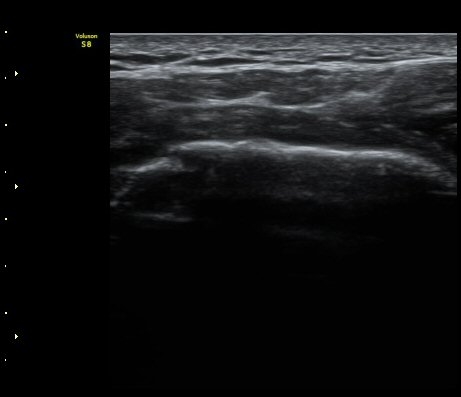

±Ø»ó°Ç Á¾´Ü¸é°Ë»ç¿¡¼­ ±Ø»ó°Ç ³»Ãø°ú ¿ÜÃø¿¡¼­ ÀüÃþÆÄ¿­ ¼Ò°ßÀ» º¸ÀÓ(½ÃÁø 1, 2).